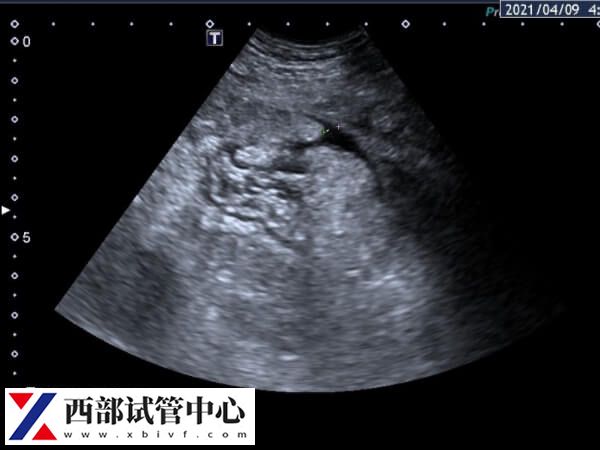

取卵后第2天肚子胀有可能是腹水的表现,可能会影响鲜胚移植,但假如只是轻微的肚子胀,并没有恶心、呕吐或腹泻等其他不适反应的话,短的话会在两三天的时间内缓解,长一点需要一周左右的时间,期间不需要进行特殊的治疗和处理,只需要做好饮食、生活习惯上的调理,保证充足休息,避免下蹲提重物、过度劳累等等,这样一般来说是不会影响鲜胚移植的。

如果取卵后肚子胀的情况比较严重,有明显的腹胀、腹围、体重增加,甚至是呼吸困难等表现,要先暂停胚胎移植,不能移植鲜胚,这时候需要将优质胚胎先冷冻起来,等腹水治好身体调理正常后再解冻移植。这种腹水的程度是中重度腹水,严重的需要做手术排出,并且还要等卵巢恢复一段时间后再移植。